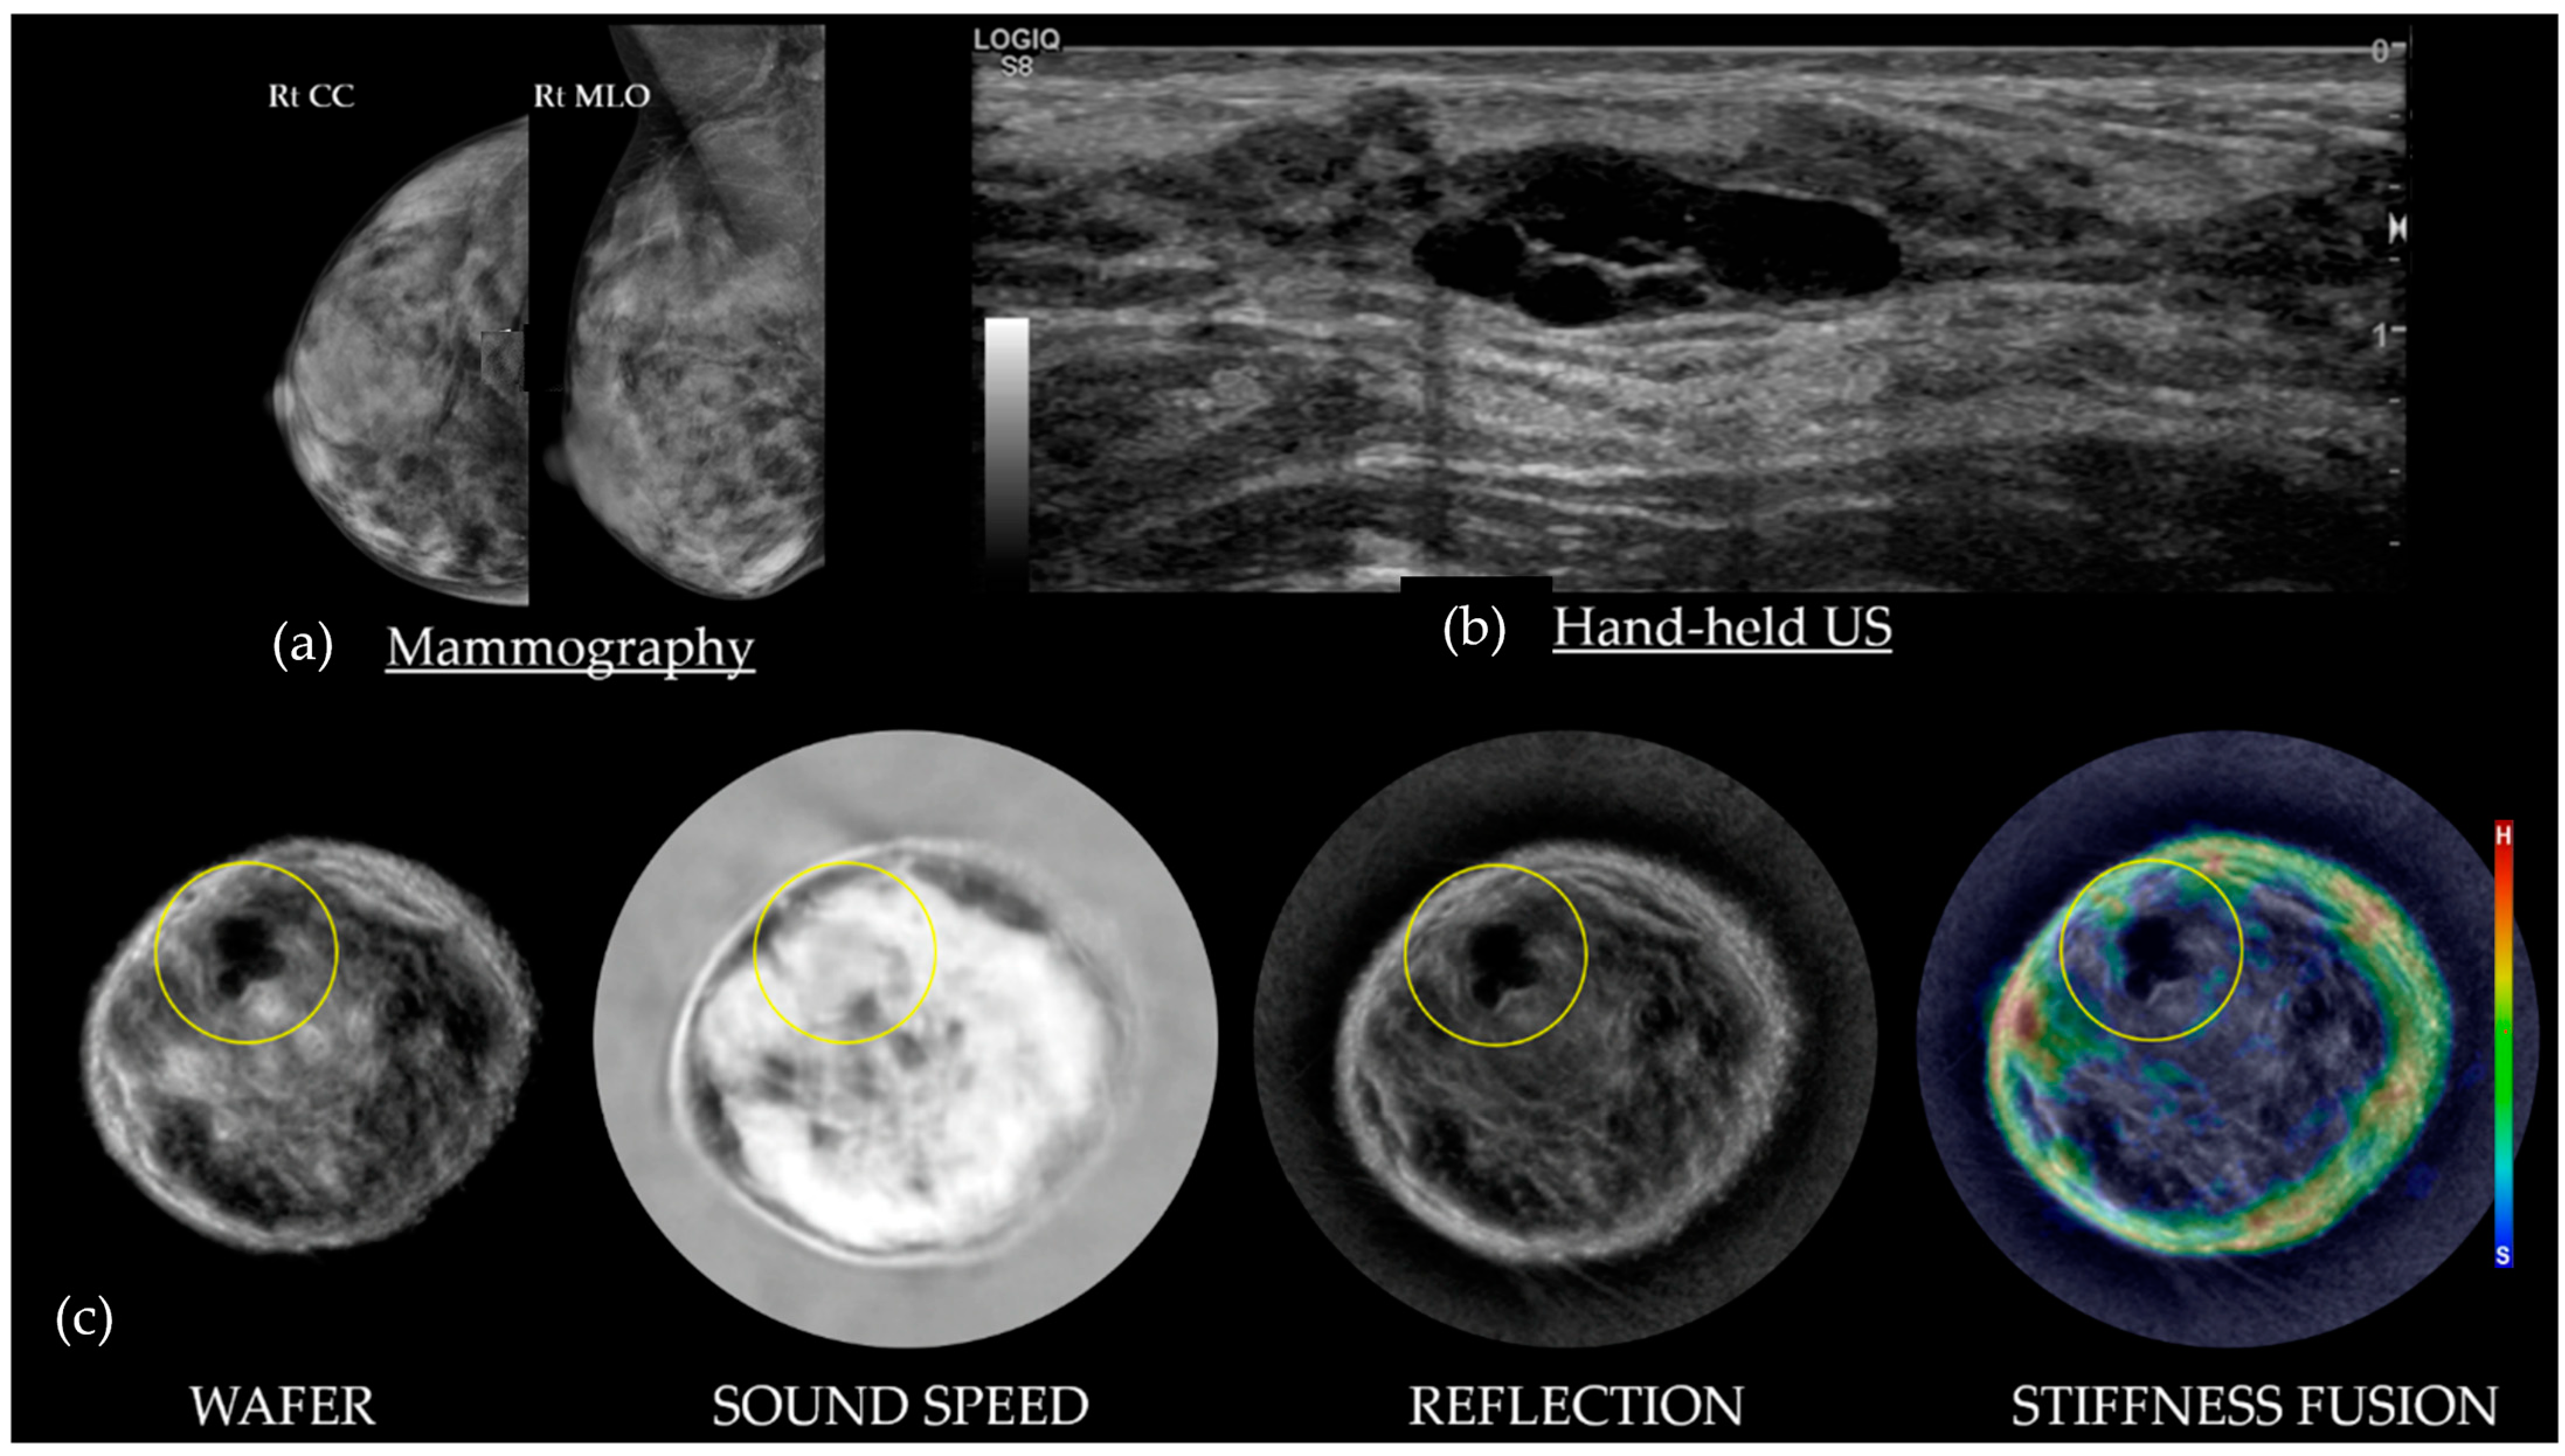

Figure 7. A 48-year-old with heterogeneously dense breasts and an ovoid 2.5 cm mass on the right mammograms (a; red arrows). An ovoid relatively homogeneous solid mass corresponding to the mammographic and palpable abnormality, seen on HHUS in the 6–7 o’clock position (b). The bottom row of SoftVue BTUS image stacks (c) shows that the fibroadenoma (yellow circles) has subtle echoes on Reflection, which become black on Wafer due to the high Sound Speed correction, and are an intermediate color on Stiffness Fusion. BI-RADS 2. (Data source: Original case from DMT’s Prospective Case Collection trial; Western IRB #DMT-2015-001).

4.2. Fibroadenomas on SoftVue

Figure 7 shows that most FAs are dark on Wafer, white on Sound Speed, and persistent on Reflection. The stiffness of a fibroadenoma can be quite variable, relative to the extent of underlying fibrosis, ranging from a hard scirrhous mass (i.e., red) to a soft parenchymal mass (i.e., blue-green). Fibroadenomas generally remain circumscribed on Stiffness Fusion, with their color(s) remaining within the margins of the mass while scrolling. Next to cancers, fibroadenomas are the most frequent mass at the fat–glandular interface (FGI), but they can also be surrounded by parenchyma [22].